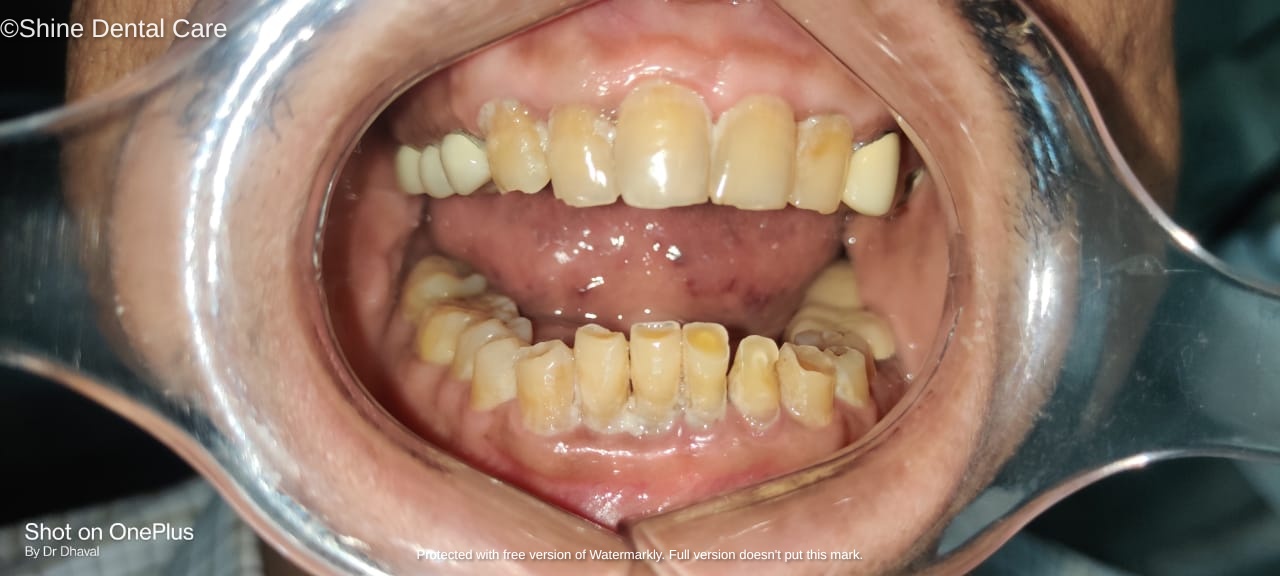

Full Mouth Rehabilitation

As the name implies, Full Mouth Rehabilitation refers to rebuilding and/or replacing all of the teeth ina patient’s mouth. Full Mouth Rehabilitations combine esthetics with the science of restorative dentistry to improve the health, function, and beauty of the mouth.

There are a number of people who have dental problems throughout their mouths that must be treated comprehensively with a vision of a final result that improves both function and esthetics. These patients may exhibit multiple missing teeth, numerous teeth with large fillings that are failing or exhibiting decay, cracked or broken teeth, or badly worn teeth due to bruxism (teeth grinding) or other habits.